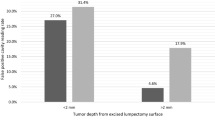

A total of 570 cavity margin surfaces in 40 patients were imaged intraoperatively and compared to excised specimen histopathology to develop the tumor detection algorithm. Image acquisition for each 2.6-cm-diameter margin surface took approximately 1 s. Invasive ductal carcinoma, invasive lobular carcinoma, invasive carcinoma with mixed ductal and lobular features and DCIS all produced similar fluorescent signals, with tumor fluorescent signal 3.78–4.11 times greater than normal tissue signal (Fig. 1). Tumor could be distinguished from normal tissue in ex vivo transected lumpectomy specimens regardless of breast mammographic density or patient menopausal status.

There were 17 surfaces that contained tumor on standard histopathology, 9 intermediate margins and 8 final margins. Tumor signal was below threshold in 3 of 17 images, all of which were intermediate cavity surfaces. For all cavity surfaces, sensitivity for tumor detection was 84%. Specificity was 73%, with some benign tissues showing elevated fluorescent signal. For intermediate margins, device readings were correlated with pathology findings in tissue excised from that site (Table 2). For the 8 patients with positive final margins after excision of the main lumpectomy specimen and standard-of-care comprehensive shaved margins, sensitivity for detection of residual tumor in the final cavity margin was 100% (Table 3).